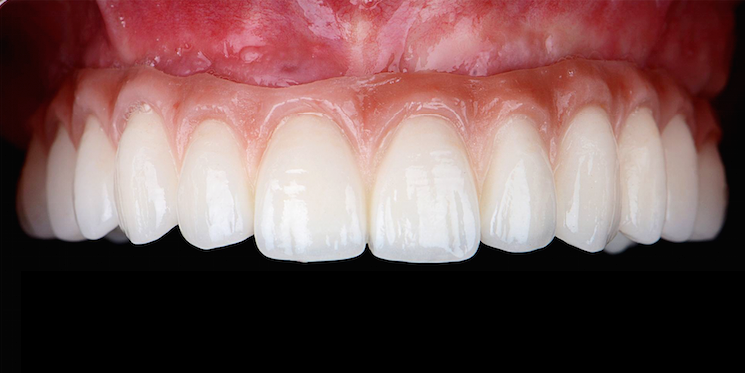

Falls Sie einen besseren Halt ihrer Prothesen wünschen, bietet sich die Möglichkeit der Verankerung ihrer Prothesen durch Implantate an.

Selbst in schwierigen Fällen wird oft eine Verbesserung erzielt und Prothesenkleber wird nicht mehr notwendig sein. Fragen Sie bei einer Beratung nach!